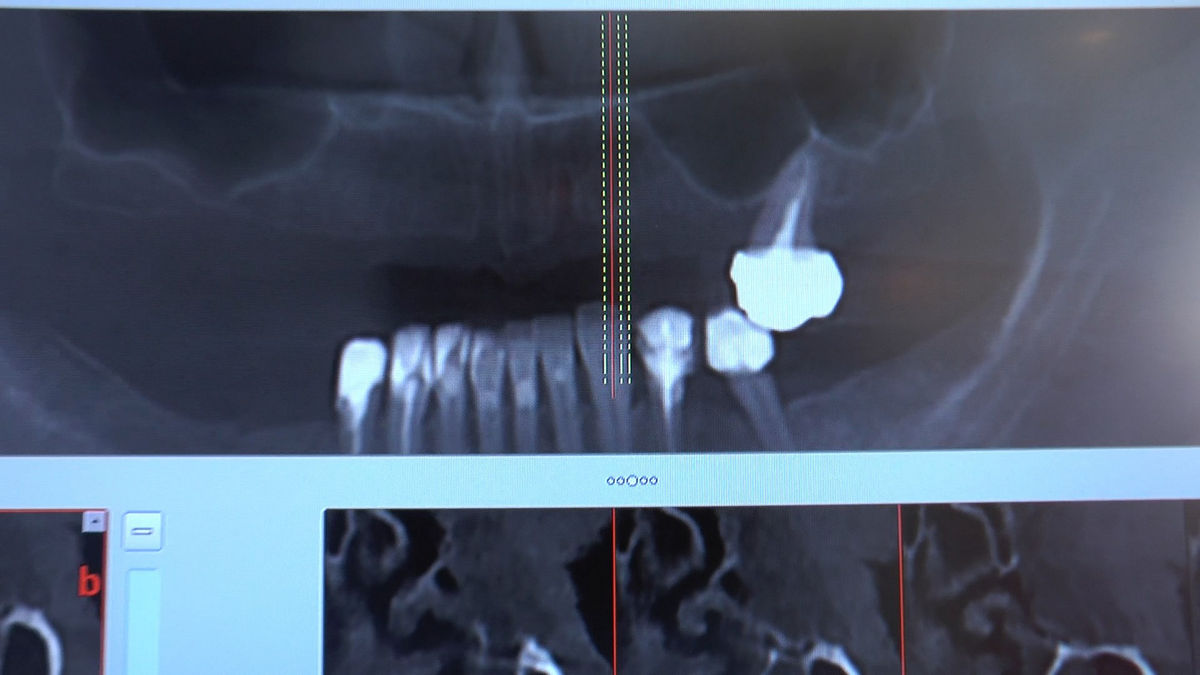

Practiculum Implantologii – Sezon V/B, sesja 8, część 4